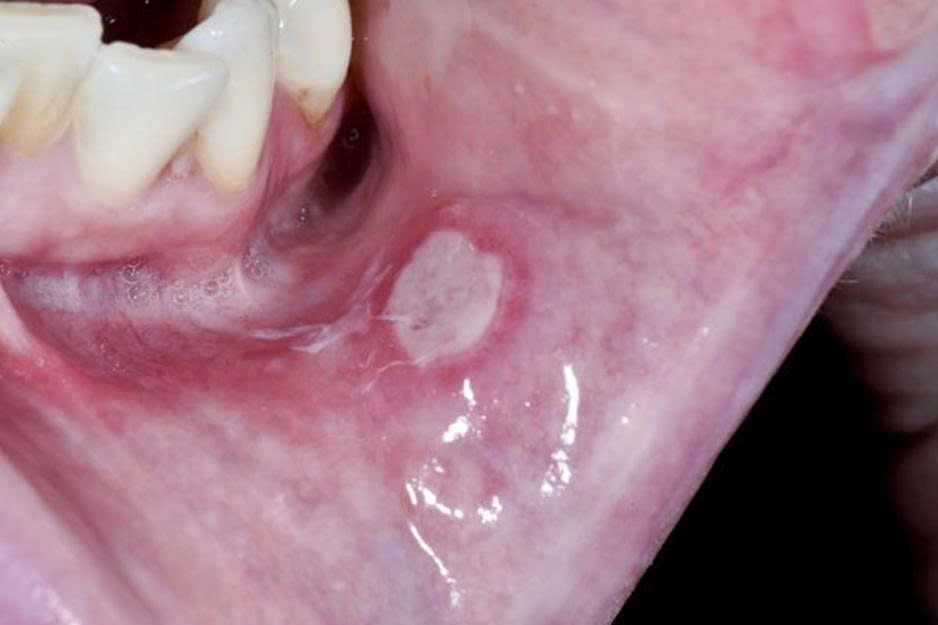

Viêm loét miệng (nhiệt miệng) là tình trạng xuất hiện các vết loét nông bên trong khoang miệng như:

- Mặt trong môi

- Má trong

- Lưỡi

- Nướu

Đặc điểm thường thấy:

- Hình tròn hoặc bầu dục

- Trung tâm trắng hoặc vàng nhạt

- Viền đỏ viêm xung quanh

- Đau khi ăn uống hoặc nói chuyện